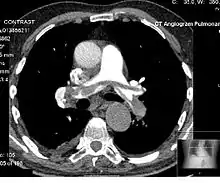

血管攝影

電腦斷層血管攝影為顯影電腦斷層掃描的一種,其針對目標血管的部位和血流相進行成像,以檢查血管疾病。例如,腹部主動脈血管攝影(abdominal aortic angiography)是在動脈相階段(顯影劑於動脈中的濃度高峰期)針對腹部的顯影,可用於檢查如主動脈剝離等症狀。[11]